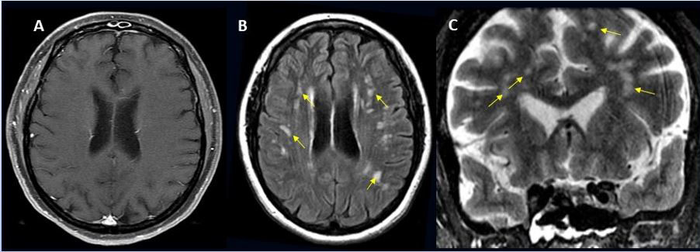

The most common brain complications were: strokes and brain bleeding, followed by brain inflammation, sinus venous thrombosis, acute demyelinating encephalomyelitis, posterior reversible encephalopathy syndrome, and vasculitis.

Image Credit: Radiological Society of North America and Scott H. Faro, M.D.